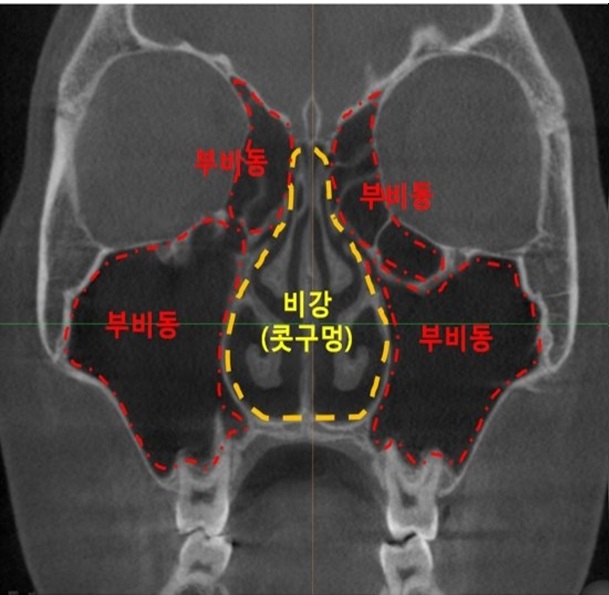

정상적인 코 CT 사진은 아래와 같습니다.

정상적인 코 CT를 보고 저희 CT를 보는데 정말 눈으로 봐도 확연히 다르게 생겼습니다.